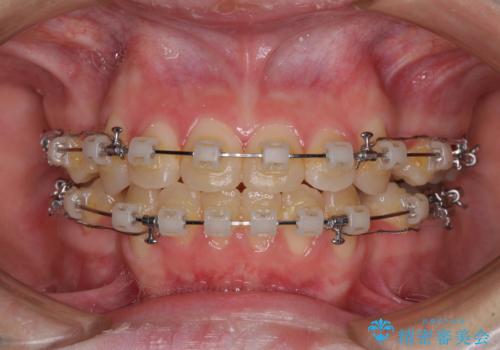

- 矯正装置

- クリアブラケット

- 上下前歯が前方に飛び出しているとのことで来院された患者様です。

上下左右第一小臼歯4本を抜歯して、積極的に口元を引っ込めるよう、ワイヤー装置にて矯正治療を行うこととしました。